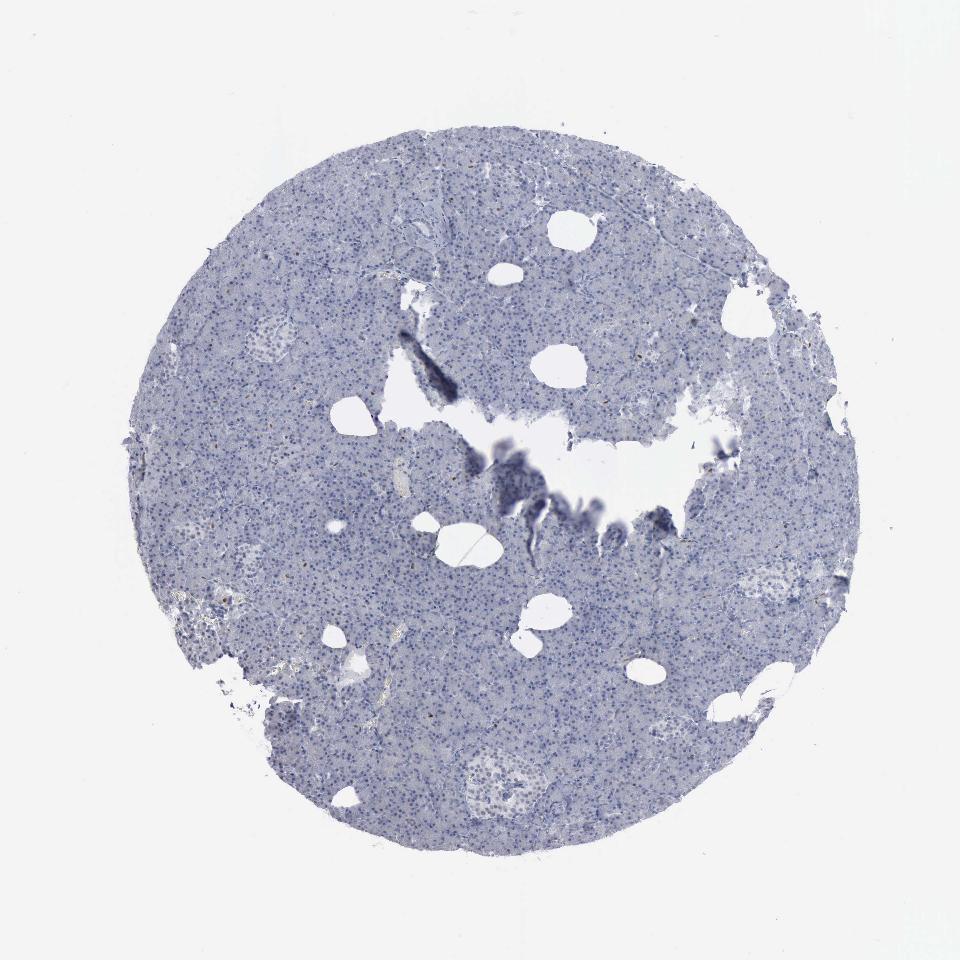

PANCREAS - Antibody stainingi

Antibody staining in the annotated cell types in the current human tissue is reported as not detected, low, medium, or high, based on conventional immunohistochemistry profiling in selected tissues. This score is based on the combination of the staining intensity and fraction of stained cells.

Each image is clickable and will lead to virtual microscopy that enables deeper exploration of all samples and also displays staining intensity scores, fraction scores and subcellular localization as well as patient and tissue information for each sample.

Antibody HPA000845Antibody CAB000101

Exocrine glandular cells MediumMedium

Pancreatic endocrine cells Not detectedNot detected